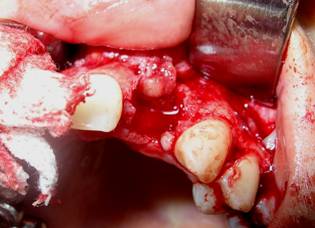

Área receptora de injerto óseo autólogo Área donante

Implante autólogo fijado en posición Colgajo reposicionado en área quirúrgica con suturas individuales

Área donante de hueso autólogo a colocar en área previa a implantar Se observan las áreas receptora y donante del injerto óseo autólogo

Colgajo reposicionado con sutura individuales Área tratada, dos semanas post cirugía